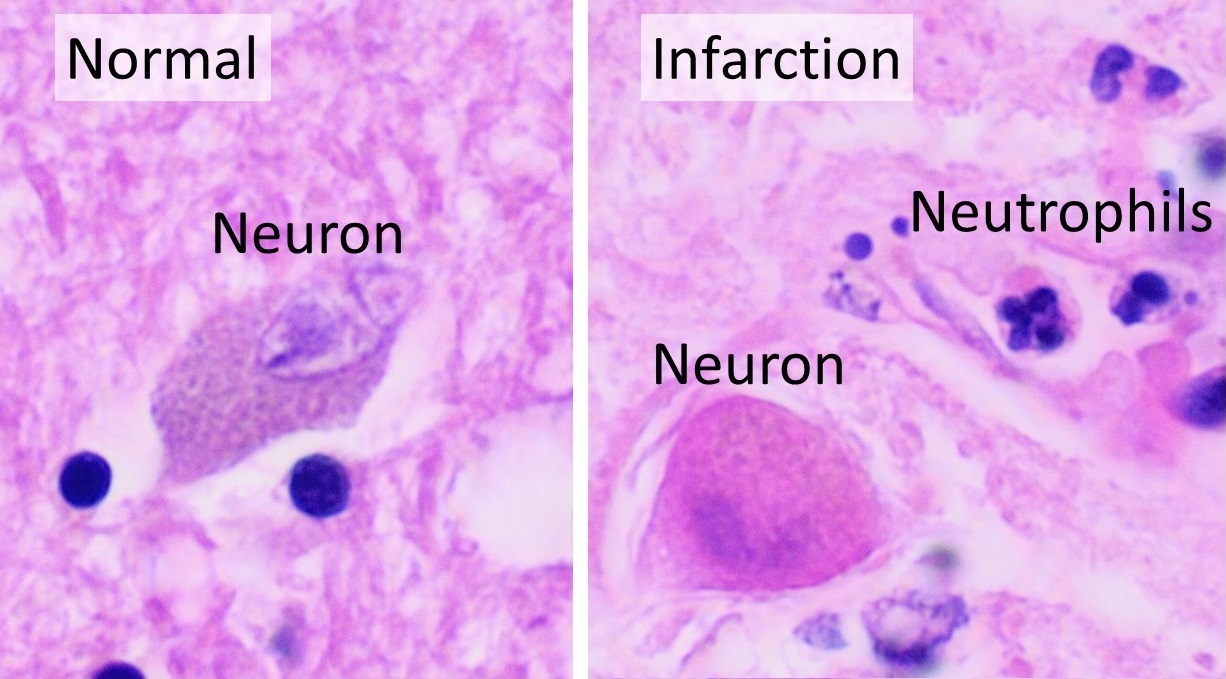

뇌혈류가 차단되면 뇌세포 활동에 필요한 에너지가 부족해진다. 이로 인해 뇌세포에서는 이온 펌프가 중단되어 뇌세포막의 탈분극이 발생하고, 무기 대사가 촉진된다. 뇌세포막 탈분극은 다량의 신경전달물질을 방출하고, 이들이 산화되면서 독성을 가진 자유 라디칼이 생성된다. 또한 뇌세포막이 탈분극되면 세포 내로 칼슘 이온이 대량 유입되어 지질 분해, 산화 질소 형성, 단백질 분해가 촉진되어 세포 손상이 일어난다.[65]뇌세포에 무기 대사가 촉진되면, 대사 산물인 젖산이 세포 내에 축적된다. 이로 인해 세포질이 산성화되면 철 이온이 유리되어 산화 라디칼 형성이 촉진되고 독성이 유발된다. 결국 이러한 기전들로 인해 뇌세포가 손상되어 대량 괴사가 일어난다.[65]

허혈성 뇌 조직에서 산소 또는 포도당이 고갈되면 아데노신 삼인산(ATP) 같은 고에너지 인산 화합물 생산이 실패한다. 이는 조직 세포 생존에 필요한 에너지 의존적 과정(예: 이온 펌핑) 실패로 이어진다. 신경세포 손상의 주요 원인은 흥분성 신경전달물질인 글루탐산 방출이다. 뇌졸중은 이온 펌프 작동을 방해하여 막을 가로지르는 이온 기울기를 감소시킨다. 글루탐산 수송체는 방향을 반대로 하여 세포외 공간으로 글루탐산을 방출한다. 글루탐산은 신경 세포 수용체(특히 NMDA 수용체)에 작용하여 칼슘 유입을 생성하고, 이는 세포의 단백질, 지질 및 핵 물질을 분해하는 효소를 활성화한다. 칼슘 유입은 미토콘드리아 기능 장애로 이어질 수 있으며, 이는 에너지 고갈로 더욱 진행되어 프로그램된 세포 사멸로 이어질 수 있다.[69]

손상 정도는 허혈 지속 시간과 심각도에 따라 달라진다. 정상의 5% 미만으로 관류가 5분 이상 지속되면 일부 뉴런이 죽게 된다. 그러나 허혈이 경미한 경우 손상은 천천히 발생하며 뇌 조직을 완전히 파괴하는 데 최대 6시간이 걸릴 수 있다. 15~30분 이상 지속되는 심한 허혈의 경우, 영향을 받은 조직 전체가 죽어 뇌경색으로 이어진다. 손상 속도는 온도의 영향을 받는데, 고열은 손상을 가속화하고 저체온증은 손상 속도를 늦춘다. 허혈 조직에 대한 혈류의 신속한 회복은 특히 조직이 아직 돌이킬 수 없이 손상되지 않은 경우 손상을 줄이거나 되돌릴 수 있다. 이는 심한 허혈 부위 주변의 중등도 허혈 부위(반암영역)에 특히 중요한데, 이 부위는 담보 혈류 때문에 여전히 회복될 가능성이 있기 때문이다.[70][71][72]

허혈성 뇌졸중은 뇌의 일부로 가는 혈액 공급이 차단되어 발생하며, 허혈 연쇄 반응을 일으킨다.[65] 동맥경화증은 혈관 내강을 좁히거나 혈전을 형성하고, 작은 색전을 방출하여 혈액 공급을 방해한다.[66] 색전성 뇌경색은 심장이나 경동맥에서 형성된 색전이 뇌혈관을 막아 발생한다. 뇌혈관이 막히면 뇌는 에너지가 부족해져 혐기성 대사를 이용하게 되는데, 이는 아데노신 삼인산(ATP)을 적게 생성하고 젖산을 생성한다. 젖산은 뇌의 산-염기 균형을 방해하고 세포를 파괴할 수 있다. 허혈 영역은 "허혈성 반그늘"이라고 불린다.[67]

산소나 포도당이 고갈된 허혈성 뇌 조직에서는 ATP와 같은 고에너지 인산 화합물 생산이 실패하고, 이는 세포 손상과 사망으로 이어진다. 신경세포 손상의 주요 원인은 흥분성 신경전달물질인 글루탐산의 방출이다. 글루탐산은 신경 세포의 수용체에 작용하여 칼슘 유입을 유발하고, 이는 세포 내 단백질, 지질 및 핵 물질을 분해하는 효소를 활성화한다. 칼슘 유입은 미토콘드리아의 기능 장애로 이어져 프로그램된 세포 사멸을 유발할 수 있다.[69]

손상의 정도는 허혈의 지속 시간과 심각도에 따라 달라진다. 정상의 5% 미만으로 관류가 5분 이상 지속되면 일부 뉴런이 죽게 되지만, 허혈이 경미한 경우 손상은 천천히 발생하여 최대 6시간이 걸릴 수 있다. 15~30분 이상 지속되는 심한 허혈의 경우, 영향을 받은 조직 전체가 죽어 뇌경색으로 이어진다. 허혈 조직에 대한 혈류의 신속한 회복은 손상을 줄이거나 되돌릴 수 있다.[70][71][72]